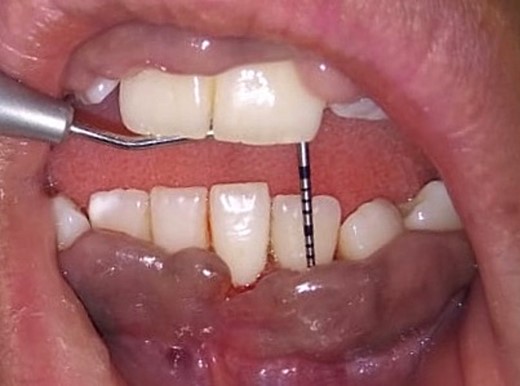

On the day of the procedure, a complete blood test was done which shows normal limit values. Following the administration of local anesthesia, periodontal pockets were checked (Fig. 2) and the bleeding points were marked using a Krane Kaplan pocket marker, (Fig. 3) continuous incision was made with the scalpel and blade no. 15, keeping the bevel at ~45° to the tooth surface. Once the incisions had been made, the excision of the tissue was done with a curette (Fig. 4). Further electrocautery was used as a coagulating machine to control the bleeding. Gingivoplasty, i.e. reshaping and recontouring of gingiva following the normal festooned pattern was done. Coe-Pak was placed and the patient was recalled after 1 week for check-up (Fig. 5).

Measuring the periodontal pocket of lower anteriors showing gingival enlargement.